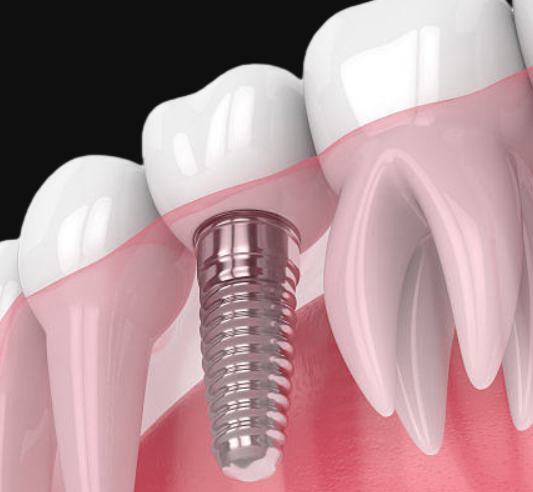

种植牙作为一种成熟的牙齿修复技术,已广泛应用于临床,帮助许多患者恢复了正常的咀嚼功能和美观。然而,对于许多人而言,种植牙是否会突然脱落依然是一个关切的问题。

种植牙通常具有较高的成功率,脱落的风险较低,但并非完全没有。了解种植牙脱落的可能性及其原因,对于患者进行有效的预防和维护至关重要。

种植牙的成功与否在很大程度上取决于种植体的初期稳定性。如果在手术后,种植体未能与牙槽骨良好融合,可能导致植入失败。在这种情况下,种植牙可能会出现松动甚至脱落。太原中诺口腔医院通过使用先进的3D影像技术进行术前评估,确保种植体的精准定位,以降低初期失败的风险。

种植体周围炎是一种种植牙常见的并发症,表现为种植体周围组织的炎症。其主要原因包括口腔卫生不良、吸烟、糖尿病等。这种炎症会导致骨质吸收,影响种植体的稳定性,严重时可能导致种植牙脱落。太原中诺口腔医院强调,术后患者需保持良好的口腔卫生,定期进行专业的洁牙,以预防种植体周围炎的发生。

不正常的咬合力可能对种植体造成过大的压力,导致种植体失稳或损坏。太原中诺口腔医院的专家会在种植牙修复过程中精细调整患者的咬合关系,确保种植牙在咀嚼时受到均匀的压力,降低种植体脱落的风险。

总体而言,种植牙的脱落风险虽然存在,但通过选择高质量的种植材料、精确的手术技术、良好的术后护理和定期的口腔检查,可以有效降低这一风险。太原中诺口腔医院凭借其专业的医疗团队和先进的设备,致力于为患者提供最优质的种植牙服务。如果您对种植牙的稳定性和脱落风险有任何疑问,建议咨询医院的专业口腔医生,以获得个性化的建议和解决方案。